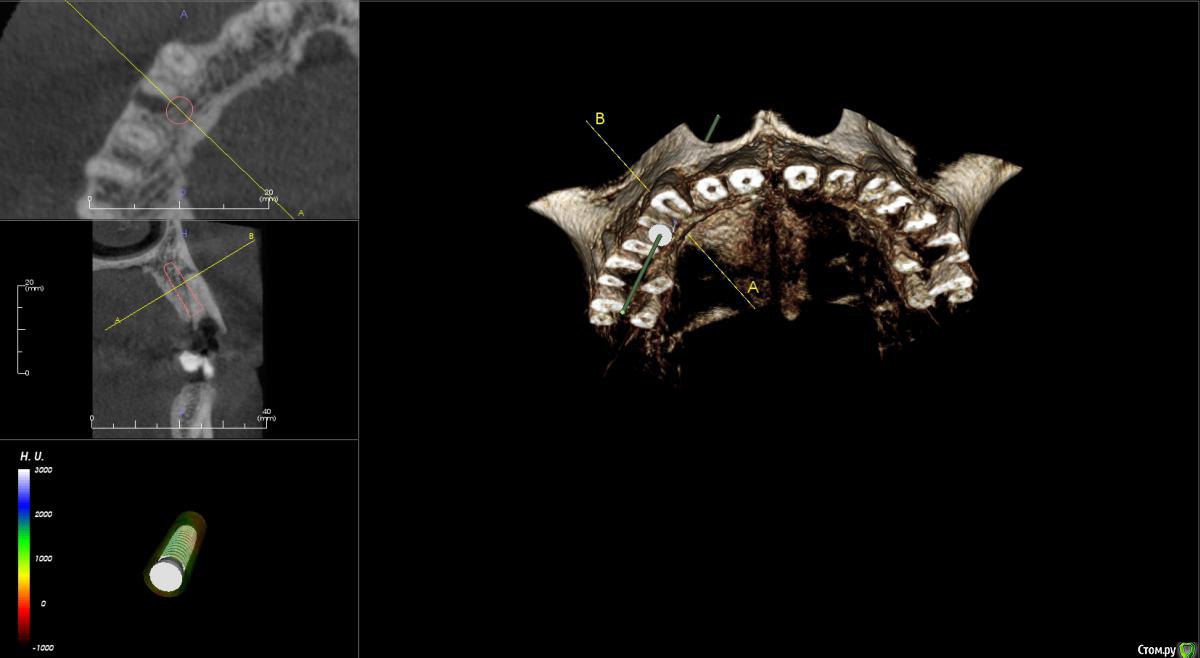

kamranchick Опубликовано 5 ноября, 2015 Поделиться Опубликовано 5 ноября, 2015 Добрый день уважаемые форумчане)Хочу посоветоваться с Вами.Пациент обратился по поводу 14 зуба, хочет удалить и поставить имплантатаБыло предложено идти но одномоментную имплантацию.Вопрос - есть ли противопоказание в данном случае? нужно ли аугментация?Я рассматриваю варианты с устновкой имплантата ALpha Bio SPI 3.3 -13мм, и установка формика с шашлычком(так как бугры хорошие), при условии хорошего торкаВаши советы... Ссылка на комментарий

faity Опубликовано 10 ноября, 2015 Поделиться Опубликовано 10 ноября, 2015 По сути переапикальные изменения обусловленны инфекцией непосредственно в каналах и после удаления причинного зуба, даже при наличии остаточной МО в костной ткани это никак не мешает приживлению импланта.Но к сожалению мои выводы основанны исключительно на литературных данных в этой области, т.к. я не дядя Карен и не имею возможности проводит гистологические исследования По топику: апекс импланта я бы немного вестибулярнее расположил, чтобы шахта выходила на бугры, а не на вестибулярную стенку и по длине такой, чтобы якорнулся в кости хотя бы на 1 мм Ссылка на комментарий

kamranchick Опубликовано 10 ноября, 2015 Автор Поделиться Опубликовано 10 ноября, 2015 По сути переапикальные изменения обусловленны инфекцией непосредственно в каналах и после удаления причинного зуба, даже при наличии остаточной МО в костной ткани это никак не мешает приживлению импланта.Но к сожалению мои выводы основанны исключительно на литературных данных в этой области, т.к. я не дядя Карен и не имею возможности проводит гистологические исследования По топику: апекс импланта я бы немного вестибулярнее расположил, чтобы шахта выходила на бугры, а не на вестибулярную стенку и по длине такой, чтобы якорнулся в кости хотя бы на 1 ммПридется выбирать. либо идти по небной стенке, либо в правильной ортопедической позиции, а можно ли сразу 2 зайца убить в данном случае? боюсь при удалении дефект будет большим. Ссылка на комментарий

faity Опубликовано 10 ноября, 2015 Поделиться Опубликовано 10 ноября, 2015 засверлитесь в правильной позиции, запакуйте графт, дойдите финишным сверлом до апекса и поставьте винт.и винт и объем и торк. сст туда посадите вообще отлично будет. Ссылка на комментарий